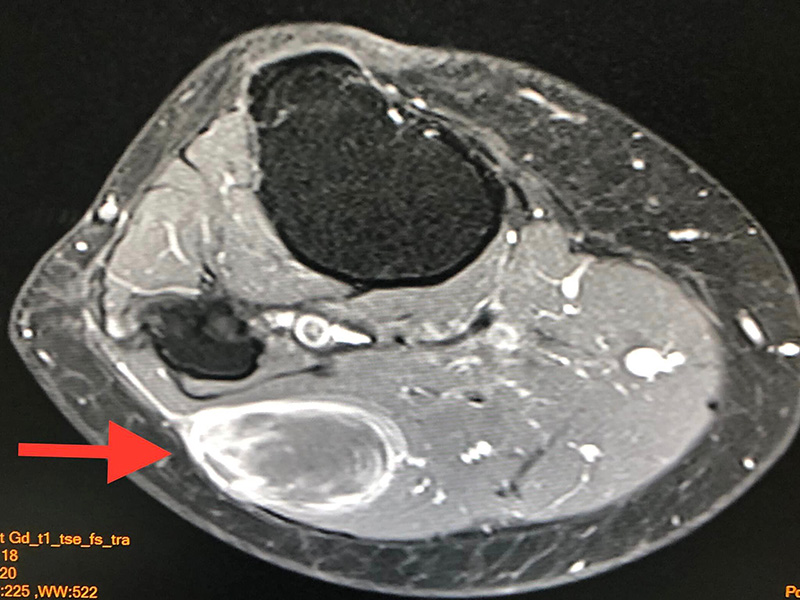

ภาพเคสตัวอย่างของ ผู้ป่วยหญิงวัย 61 ปี กับขั้นตอนการรักษา จากวันที่ตรวจพบก้อนเนื้อร้าย จนปัจจุบันหายดีแล้ว

- ผู้ป่วยหญิงอายุ 61 ปี ปกติแข็งแรงดี คลำได้ก้อนที่ขาใต้หัวเข่าข้างขวาด้านนอกขนาด 5 เซนติเมตร ก้อนนูนแข็ง ขยับก้อนได้ค่อย ๆ โตขึ้น ไม่เจ็บ

- เดือนมีนาคม 2565 ทำ MRI ตรวจคลื่นแม่เหล็กไฟฟ้า พบก้อนขนาด 3.5 x 2.2 x 5.1 เซนติเมตร อยู่ชั้นใต้ผิวหนังติดกับกล้ามเนื้อของขา สงสัยมะเร็งเนื้อเยื่ออ่อน (soft tissue sarcoma)